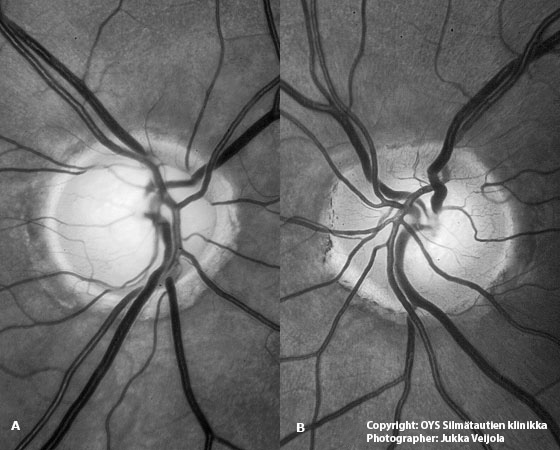

Enlarged optic nerve cup in open-angle glaucoma. The appearance of the optic nerve head is asymmetric between right (A) and left (B) eye. The optic nerve cup in the right eye is enlarged and the colour is paler than in the neighbouring eye.

Picture: Jukka Veijola, text: Anja Tuulonen